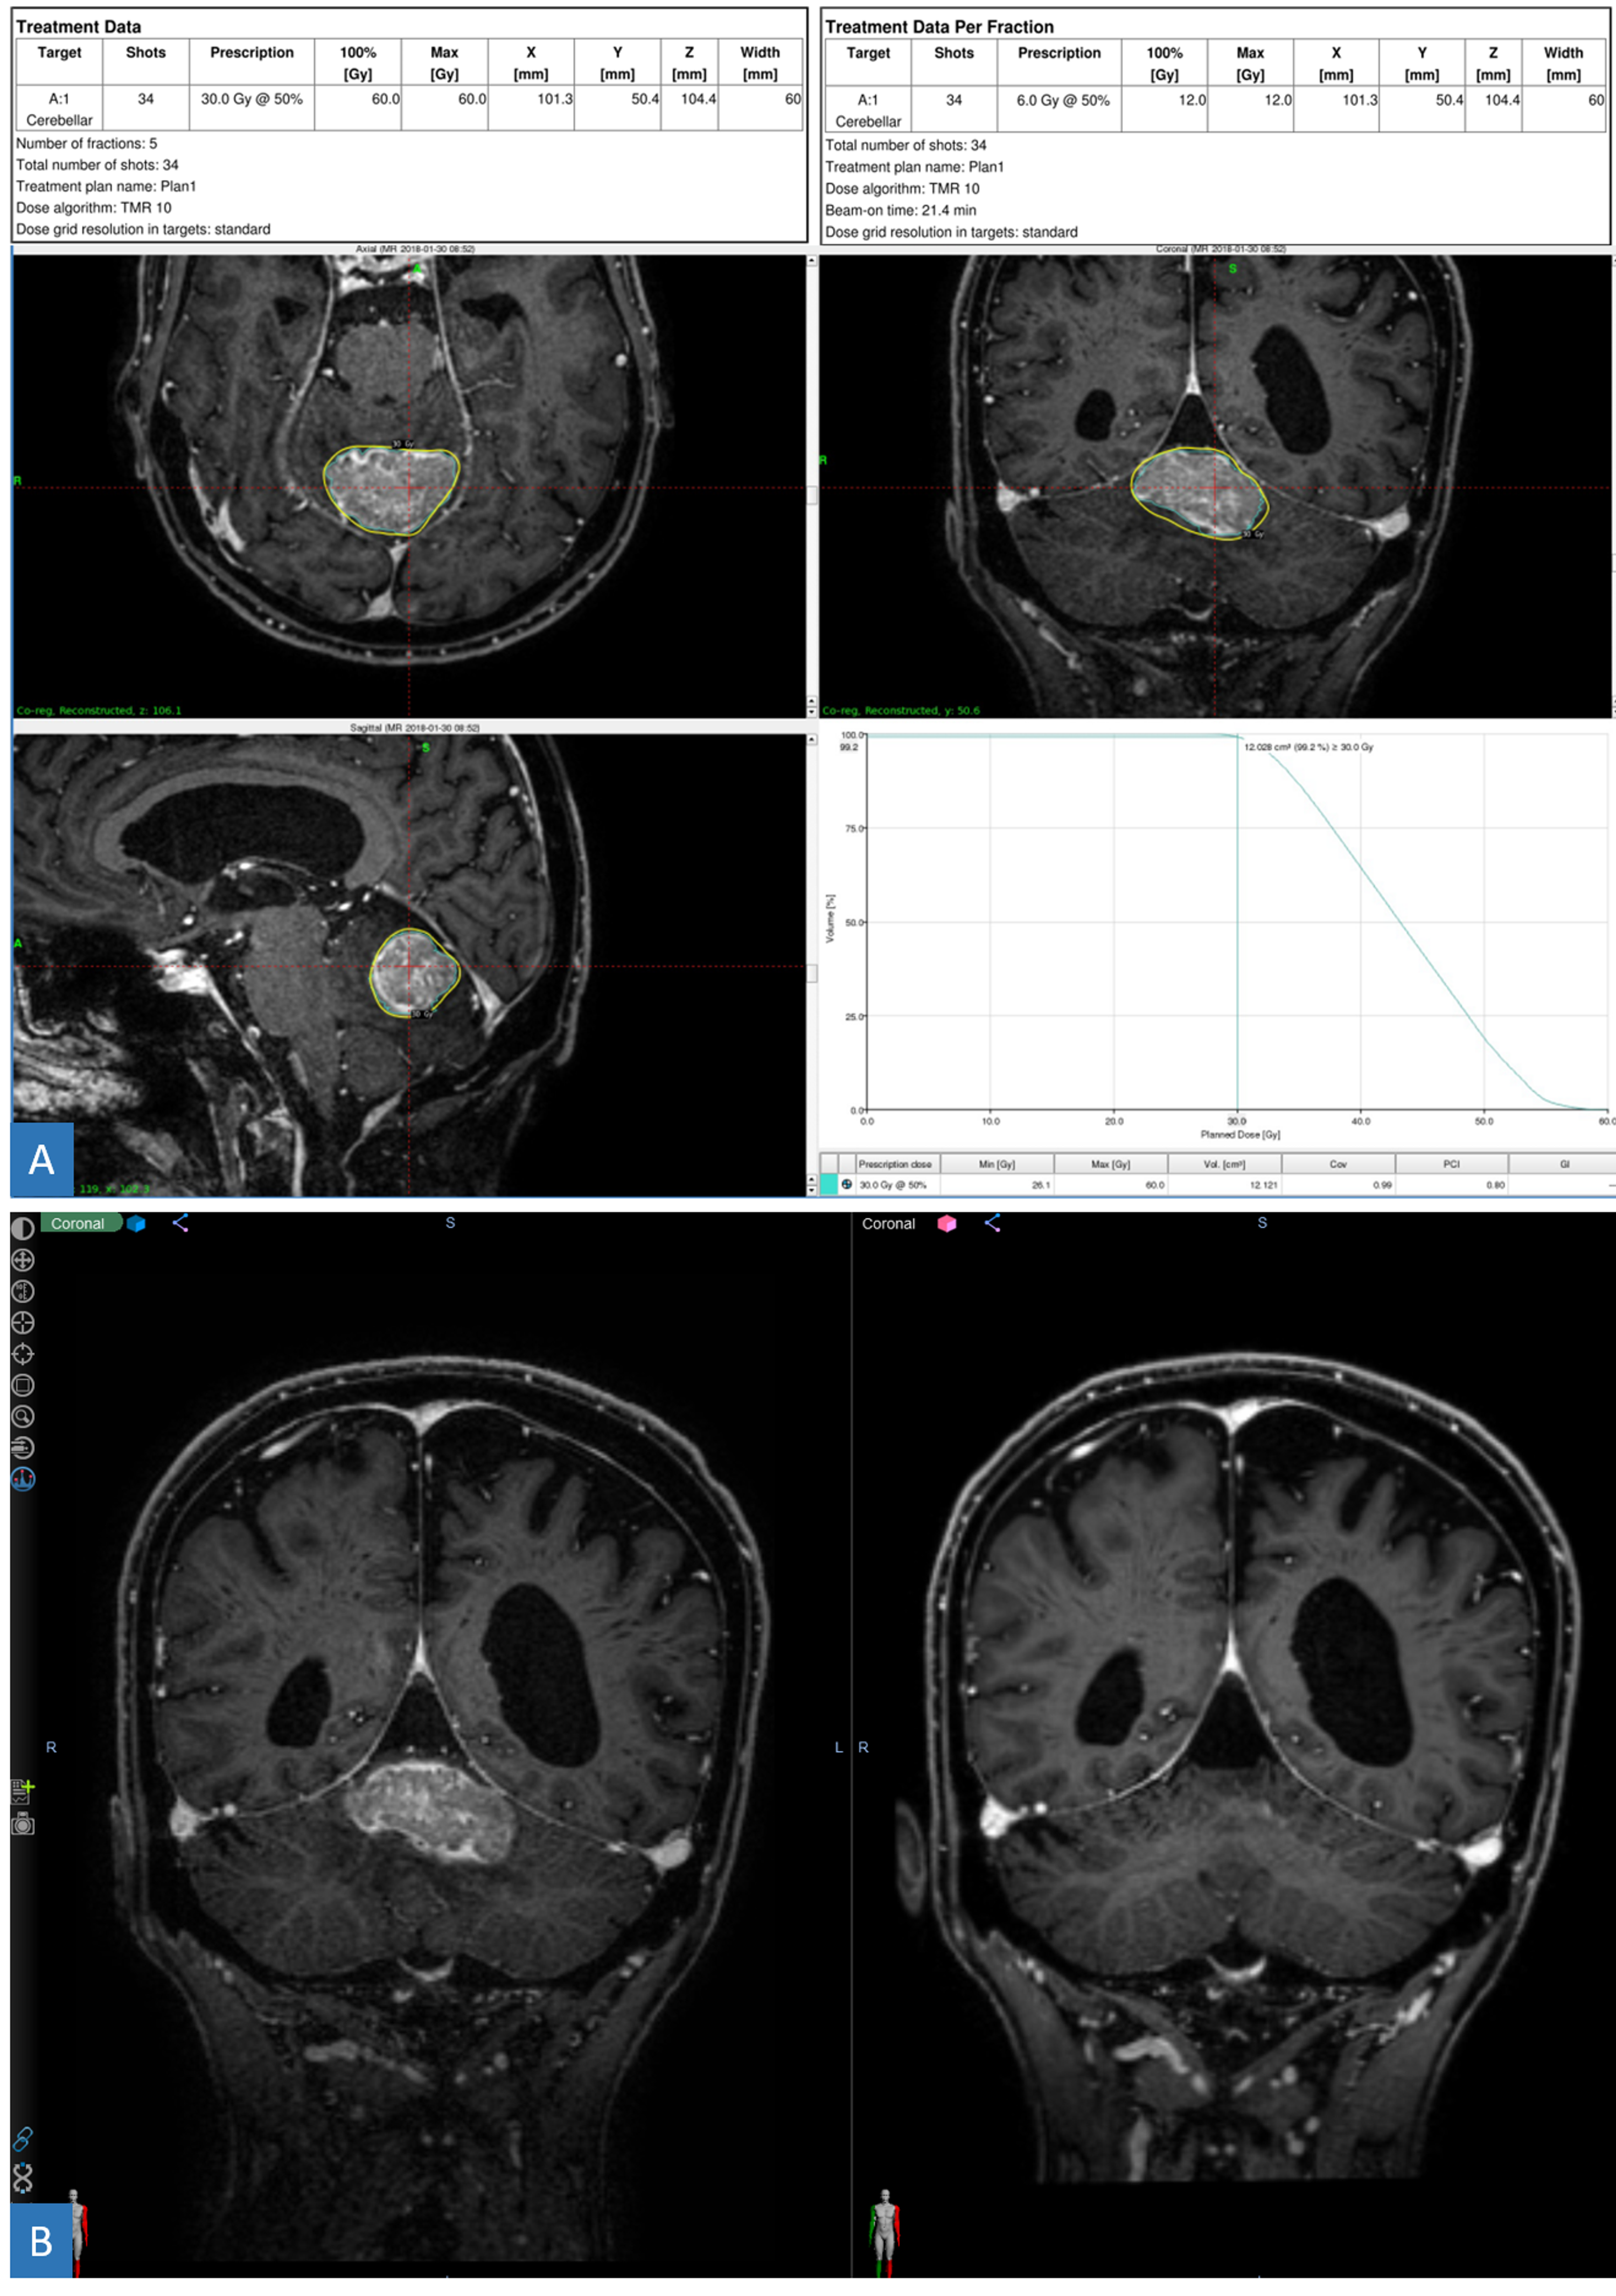

Source: cureus.com